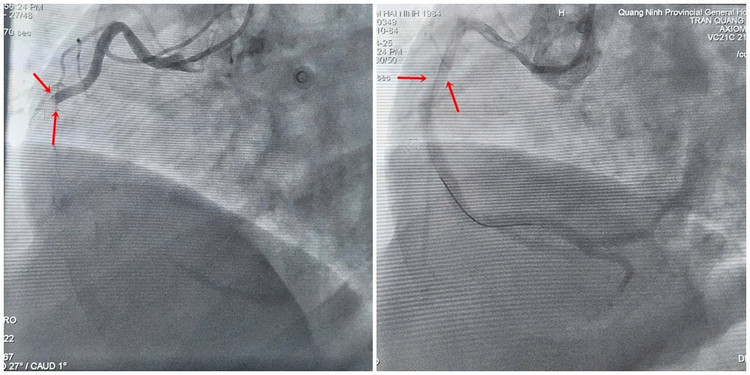

Hình ảnh tắc hoàn toàn động mạch vành phải trước và sau khi được lấy huyết khối, can thiệp đặt stent tái thông lòng mạch - Ảnh BVCC

Kíp can thiệp do BSCKII Trần Quang Định, Trưởng khoa Phẫu thuật và Can thiệp tim mạch cùng các cộng sự được huy động để thực hiện can thiệp cấp cứu cho người bệnh. Kết quả chụp mạch cho thấy huyết khối gây tắc hoàn toàn động mạch vành phải.

Sau nỗ lực cấp cứu căng thẳng, tim hồi phục nhịp đập trở lại. Kíp can thiệp tiếp tục thực hiện đặt stent để tái thông lòng mạch bị hẹp tắc, khôi phục tưới máu cho cơ tim.